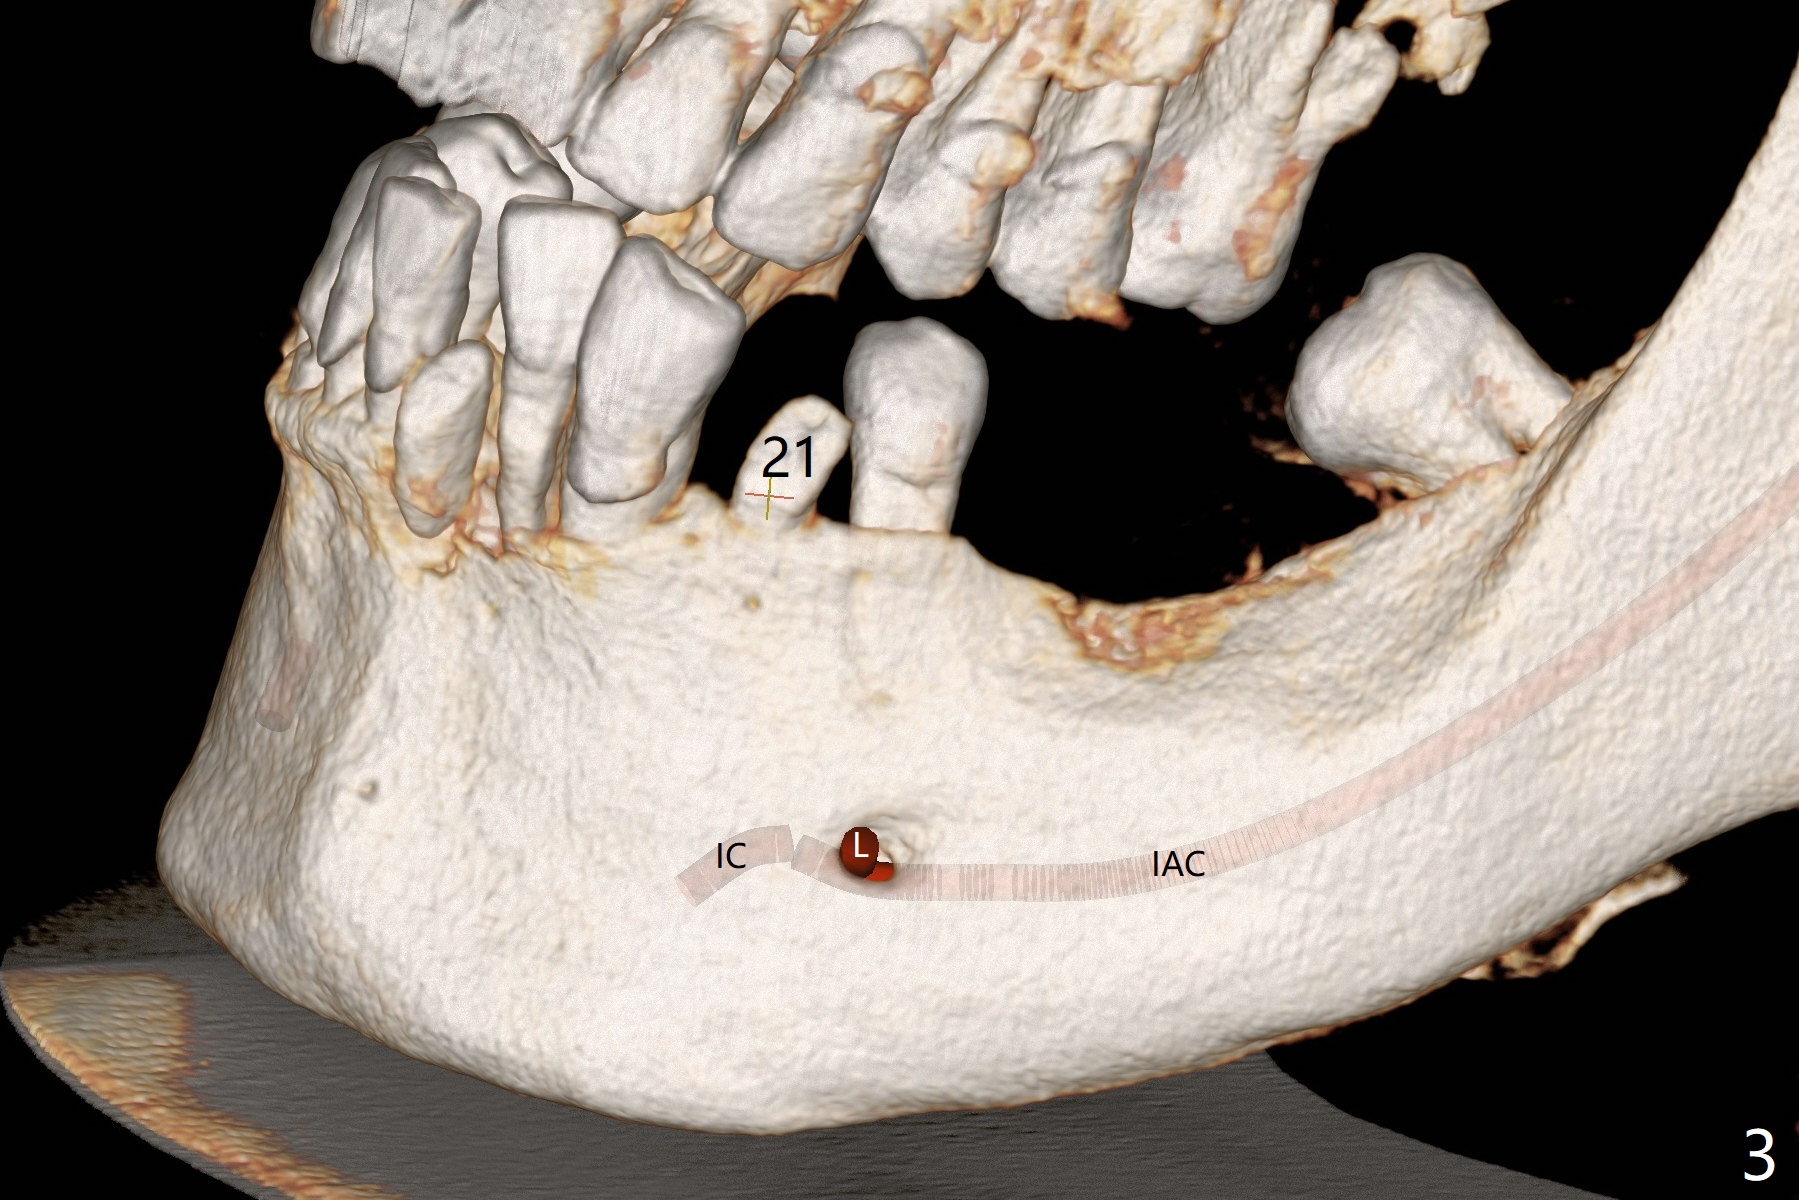

A 54-year-old man has poor dentition, including missing tooth of #19 and residual root at #20 (Fig.1). The lingual crest (Fig.2 (lingual view), Fig.4 (L)) is lower than the buccal one. The Inferior Alveolar Canal (Fig.3 IAC) becomes the Incisive Canal (IC, Fig.4 red circle) after the Mental Loop (Foramen). An implant at #21 will be placed at the level between the buccal and lingual crests (Fig.4) with osteotomy initiated in the middle of the socket. Bone graft is to be placed around the coronal end of the implant (yellow circles).

The socket at #19 appears to have not completely ossified (Fig.1 *, Fig.5). Use Magic Split and Magic Expanders to expand the ridge top so that an implant will be placed higher for favorable crown/implant ratio (reduce abutment screw loosening). Note the concavity at the site of #19 while osteotomy (Fig.2 *).